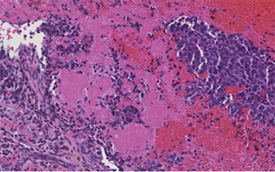

A 38-year-old female patient was admitted for a predominantly painful tetraparesthesia of the upper limbs with three months of history, associated with a left hemiparesis. He was also associated with episodes of vagal discomfort, asthenia, unencrypted hyperthermia, respiratory discomfort and relative impotence of the left-wing progressive build-up. The clinical examination found an asythenic, adynamic patient, a tetrapyramidal syndrome with a non-proportional left hemiparesis respecting the face, rated at three out of five (3/5) in the upper limb and two out of five (2/5) in the lower limb, as well as a Babinski sign on the left. The osteotendinous reflexes were lively. He had also been found on the examination a sensitive level thoracic T4 and discrete proprioceptive disorders left. MRI of the cervical spine showed extensive cervical extra-medullary intradural lesion of C3 to C5 with significant medullary edema (Figures 1(a)-1(c)). A discretely hyperintense T1 lesion moderately enhances gadolinium. The treatment was posterior cervicotomy resection surgery, C3 to C5 laminectomy. In intradural exploration, a well-defined lesion, of firm consistency, lateralised on the left with a pre-medullary anterior extension which did not seem to infiltrate the marrow or engulf the nerve roots, had been discovered. Exeresis appeared macroscopically complete, but postoperative MRI showed a moderately compressive tumor residue (Figure 1(d)). A surgical reoperation by the same route initially was made four (4) weeks after the first surgery. It persisted a tumor residue on the MRI control. The postoperative course was marked by a complete recovery of traction and transient episodes of spasm of the left upper limb regressed under benzodiazepines. Histological examination of the lesion revealed a tumor proliferation of dense cellularity, with foci of necrosis, oval cells organized in large compact plates and pseudo-rosettes. The nucleo-cytoplasmic ratio was high. The nuclei appeared voluminous, irregular, and possessing a mottled chromatin. Mitosis Figures are visible on ten (10) out of fourteen (14) fields at forty (40) magnification as well as apoptotic bodies (Figure 2). Immunohistochemical analysis was performed on the operative part. The pathological cells expressed a high immunopositivity to the GFAP gliofibrillar acid protein and PS 100. EMA membrane epithelial antigen had shown focal labeling of tumor proliferation to cytoplasmic dot while proliferation index Ki-67 showed Heterogeneous labeling in the form of hot spot focus with 50% of labeled tumor cells. These pieces of information led to the conclusion of the diagnosis of grade III anaplastic ependymoma.

Figure 2. Histological cross-section Magnification of X40 images. Histological features of the ependymomas observed. Prerivascular pseudorosette were identified (H & E, x200). The tumor exhibit slightly necrosis and High proliferative activity. (a) Pseudo rosette; (b) Necros; (c) Mitose; (d) Anaplasticependymoma.